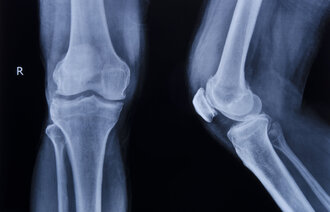

Ved det store ortopediske sykehuset RNIITO (Vreden Russian Research Institute of Traumatology and Orthopedics) i St. Petersburg, har Lindberg, sammen med blant andre UiO-professor Anners Lerdal, bidratt til en studie av smerteforløp, funksjon og livskvalitet hos pasienter som gjennomgår kneproteseoperasjoner.

Fra russisk side har lederen av knekirurgiavdelingen ved RNIITO, ortopeden Nickolay Kornilov, vært ansvarlig for gjennomføringen av studien, som er basert på en tilsvarende undersøkelse Lindberg ledet ved Lovisenberg Diakonale Sykehus i Oslo.

I grove trekk viste studien svært høy smerteintensitet hos pasientene. Lengre operasjonstid ga høyere smerteintensitet i etterkant, og studien konkluderte med at smertebehandlingen som ble gitt, var mangelfull.

Ledelsen ved RNIITO ønsker nå å innføre tiltak for å lindre postoperative smerter og la de kneopererte pasientene raskere gjenvinne funksjon. Ledelsesgruppen har også tatt initiativ til samarbeid om nye smerteforskningsstudier på sykehuset.